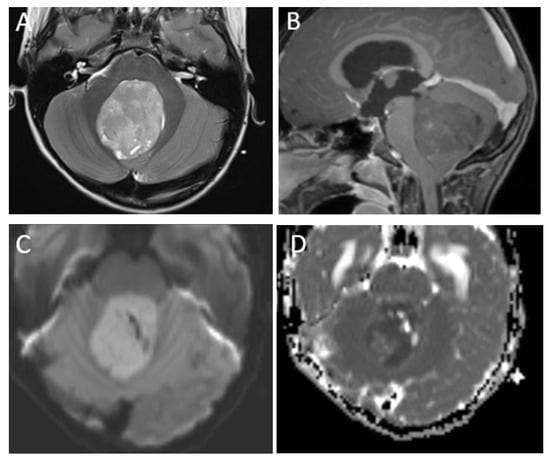

Figure 1.

A 7-year-old boy with medulloblastoma. Axial T2 (A), sagittal post-contrast T1 (B), images demonstrate a mildly heterogeneous midline posterior fossa mass. DWI (C) and ADC (D) imaging demonstrates diffusion restriction of the lesion relative to the adjacent cerebellar parenchyma, typical of these highly cellular neoplasms. Perfusion imaging (E) demonstrates increased relative cerebral blood volume within the lesion and MRS (F) demonstrates a high choline peak (long arrow) as well as a small taurine peak (short arrow).